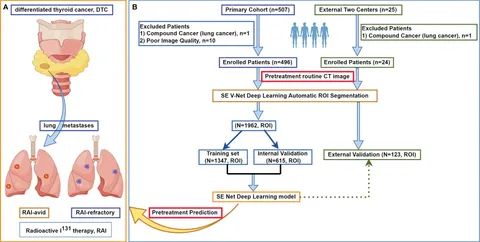

Diagnostic Strategies for Thyroid Nodules Based on

Diagnostic Strategies for Thyroid Nodules Based on